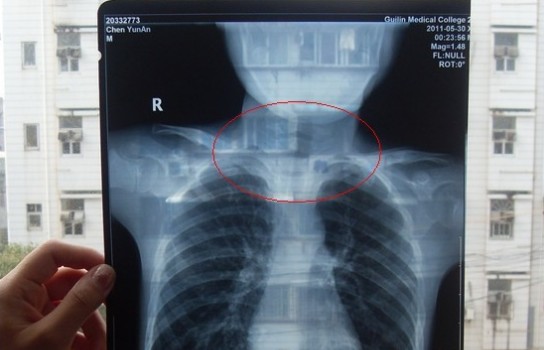

胸部正位X光片圖

2011年5月29日下午,陳先生的兒子安安出現(xiàn)嘔吐、肚子疼痛等癥狀。陳先生立即將兒子送往醫(yī)學(xué)院附院,根據(jù)醫(yī)生開出的會(huì)診單,分別對(duì)安安做了腹部立臥位2次和胸部正位1次共3次X光片檢查、診斷。醫(yī)生看X光片后排除了腸梗阻病因,判斷是闌尾炎。經(jīng)過治療,不久安安身體痊愈。

可是,陳先生的一次偶然發(fā)現(xiàn),讓他們一家過上了提心吊膽的日子。因?yàn)?,在安安出院一個(gè)月后,陳先生偶然翻出孩子治療期間的X光片。發(fā)現(xiàn)在X光片中,孩子的生殖器官以及甲狀腺等敏感部位也在被放射區(qū)域中。而陳先生上網(wǎng)查到:人體拍攝X光片是有一定輻射的,并且輻射有可能引起基因變異等問題,他立馬陷入恐慌中。

至于,為什么拍攝X光時(shí),孩子的敏感部位也在放射區(qū)域內(nèi),這讓陳先生百思不得其解。為此,他專門到醫(yī)學(xué)院進(jìn)行了質(zhì)疑。而醫(yī)院的醫(yī)務(wù)人員說,拍腹部X光片就要照到睪丸,要檢查睪丸是否正常,而且怕小孩亂動(dòng),所以要照寬些。